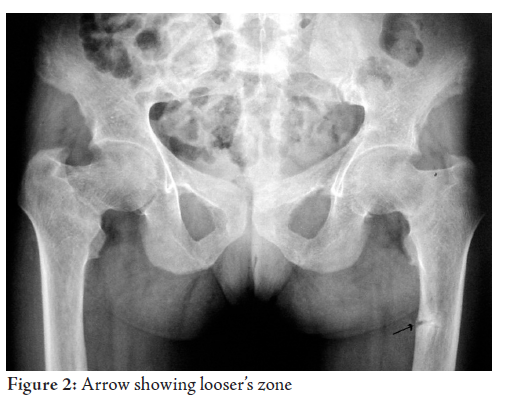

How is osteomalacia investigated?